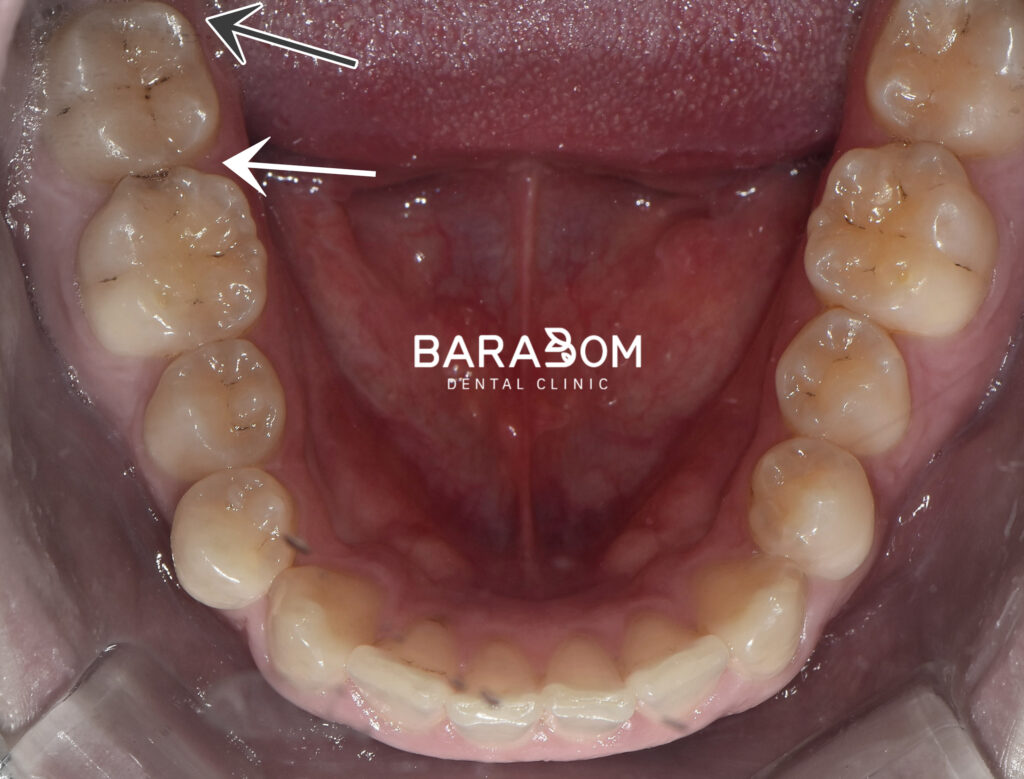

구강 내 모습을 먼저 확인해 보겠습니다.

전체적으로 잇몸 염증이 나타나

치은이 발적된 것을 확인됩니다.

치아 곳곳에 충치와 치석 변색이 나타나 있습니다.